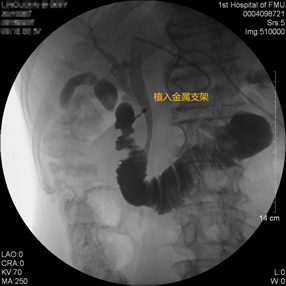

胃毕-Ⅱ术后肝门部胆管狭窄 胃毕-Ⅱ术后金属支架植入

胃毕-Ⅱ术后胰管胆管双支架植入 胃毕-Ⅱ术后胆管金属支架植入